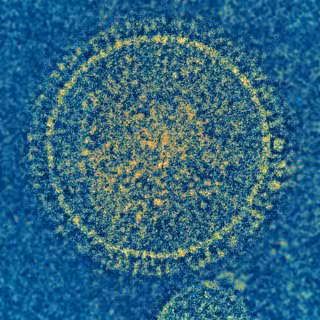

Diseñan una vacuna que genera potentes anticuerpos contra el virus respiratorio sincitial

Virus sincitial respiratorio

NIAID - Archivo

En un esfuerzo de investigación internacional, científicos han diseñado una vacuna de nanopartículas para el virus sincitial respiratorio (VSR), que solo es superado por la malaria como causa de mortalidad infantil en todo el mundo. La nueva vacuna produce potentes anticuerpos neutralizantes contra el VRS en ratones y monos, según un artículo publicado este jueves en la revista 'Cell', en el que se informa de los resultados de la investigación en animales.

Igual que un balón de fútbol de cuero que está formado por patrones geométricos cosidos, el núcleo de la nueva vacuna es una nanopartícula diseñada por ordenador hecha de diferentes partes en forma de pentágonos y triángulos. Cada nanopartícula es más de diez millones de veces más pequeña que una semilla de amapola. El exterior de estas nanopartículas se equipó con proteínas inertes del VRS para crear la vacuna.